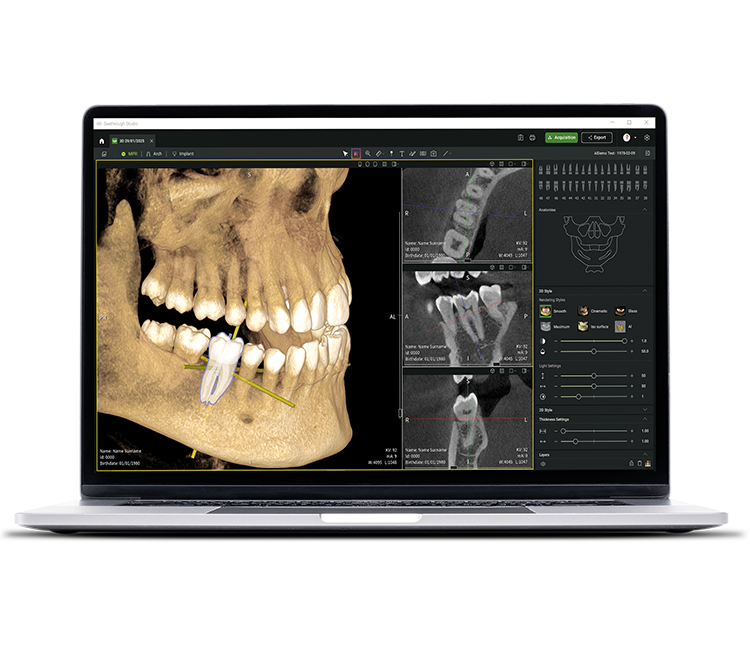

• Seethrough Studio

See tomorrow. See a new level.

Además de las sofisticadas tecnologías de hardware, el revolucionario software Seethrough Studio es el factor decisivo para el alto nivel de toda la gama de productos radiológicos de W&H. Con funciones útiles y algoritmos avanzados, Seethrough Studio es una solución completa que lleva los flujos de trabajo digitales y de radiología en odontología a un nuevo nivel.

Herramienta de planificación de implantes integrada

Además de la excelente calidad de imagen y el uso intuitivo, Seethrough Studio ofrece numerosas funciones útiles, como la herramienta de planificación de implantes integrada de serie para facilitar la visualización y la preparación del tratamiento.

Funciones asistidas por IA